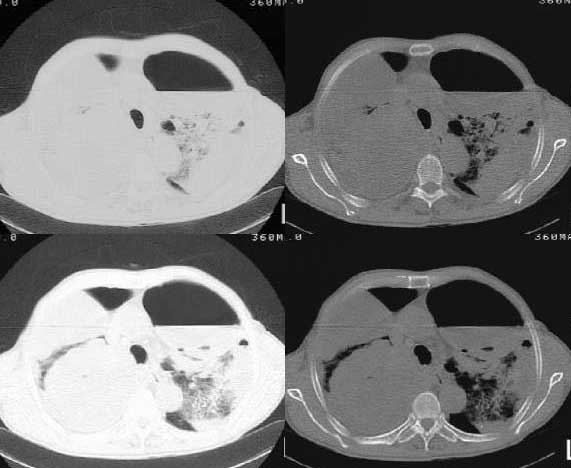

以下是引用woaixct在2006-6-23 12:15:00的发言:[br]第一张胸片示:右肺上叶为大片致密影占据,左肺上见大片致影及空洞性病灶并有液平;[br]第二张胸片示:左肺上叶致密影及空洞性病灶基本吸收,而右肺上叶之病灶有少许吸收改变;[br]ct片示:右上叶大片软组织密度,右肺门区至右肺上叶见巨大软组织块,内见支气管充气征,上纵隔右移,主气管及上叶支气受压变扁,中间支气管狭窄,左肺上叶空洞性病灶并有液平,左肺上叶尖后段见大片致密影,结合2张胸片考虑,ct片是4月份所摄,而不是6月份的片子;[br]结合2张胸片及ct片考虑:[br] 1.右中央型肺癌伴右肺上叶不张;[br] 2.左肺上叶尖后段炎性变及左肺脓肿;[br]第2张胸片提示:经过一个多月的不规则抗炎治疗,左肺上叶病灶及右肺上叶不张病灶基本吸收,而右肺占位无明显变化。

以下是引用jiangjing在2006-6-23 21:21:00的发言:[br]个人考虑还是两肺感染性病变可能大,主支气管及叶支气管是通畅的,并可见支气管气相;ct提示病变是以肺叶分布的,密度相对均匀;胸片可见有叶间裂下坠征,是不是考虑克雷伯杆菌感染可能.病人前后两张片比较病变是增多[应该考虑混合感染可能性大,右肺癌待排建议查痰及穿刺检查]